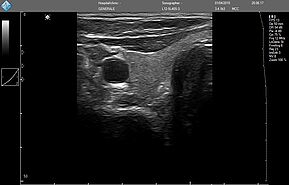

ЗДЕСЬ Вы можете посмотреть реальные кинопетли с аппарата УЗИ MicrUs Pro.